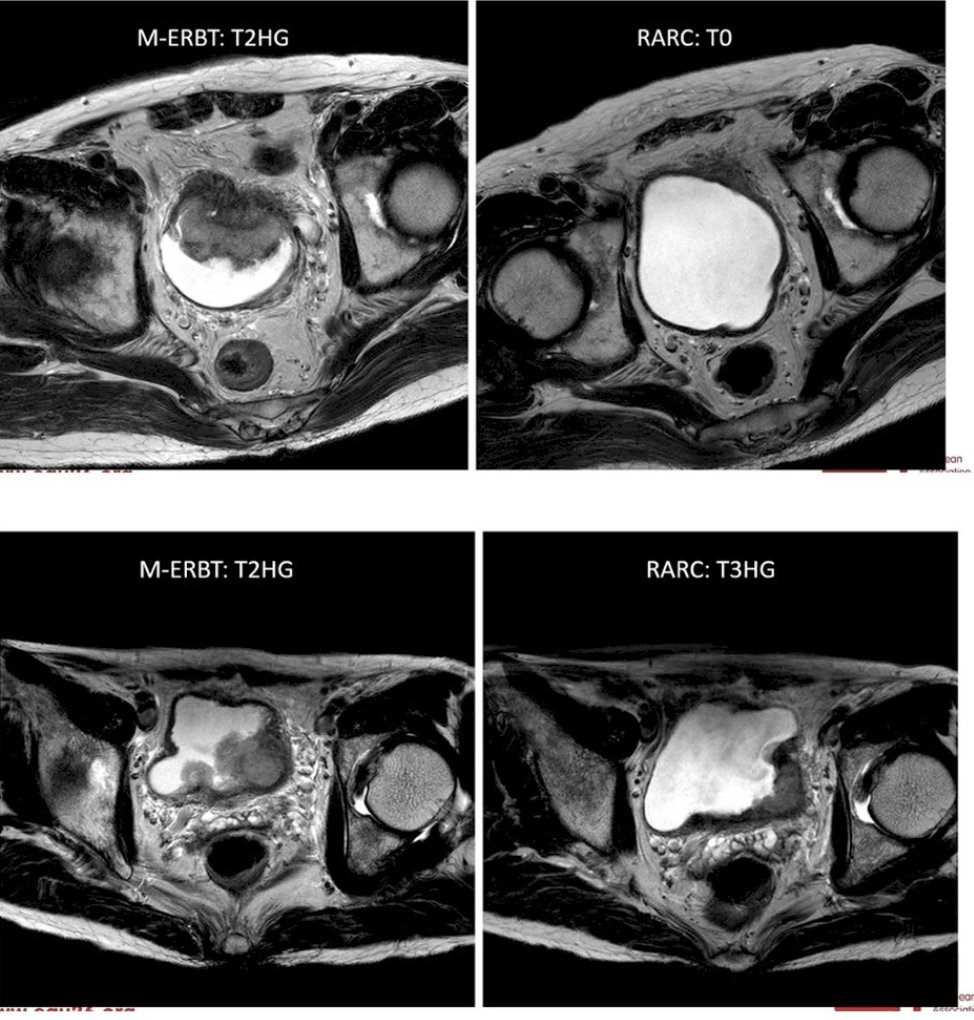

Extremely excited to share our latest article published @TheLancetOncol a few hours ago: authors.elsevier.com/a/1mYT65EIIgTS…. The WOLVERINE individual patient meta-analysis was an international collaboration and part of X-MET collaboration. Goal was to evaluate MDT in oligomet prostate ca.